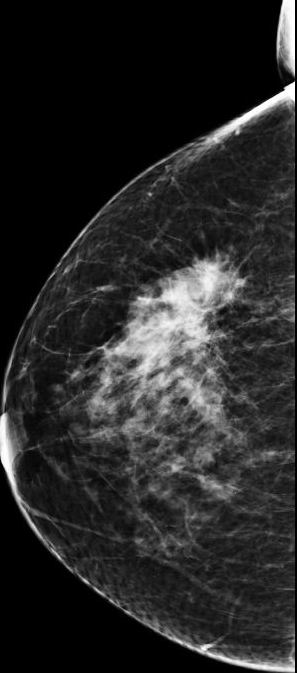

Bi-rads 4 means that the findings on the image are suspicious and that there is an approximately 20 percent to 35 percent chance that a breast cancer is present.

We proceed to calculate the volume of the tumor contained in the breast from the following Bi-rads 4 breast images.

Similarly, we use the same algorithm to evaluate the tumor volume for 4 Bi-rads 4 images and the results are the following:

| Bi-rads 4 Image | Optimal Threshold | Tumor Volume |

|---|---|---|

| Image 1 | 120.574 | 11% of breast volume |

| Image 2 | 59.9143 | 45% of breast volume |

| Image 3 | 239.696 | 0.24% of breast volume |

| Image 4 | 244.590 | 0.0287% of breast volume |